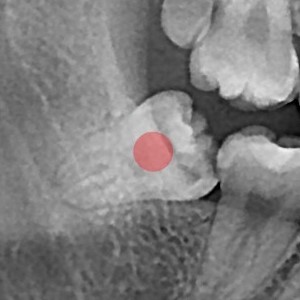

智齿拔除 严重龋坏的智齿

b047bd763797d0ee5fe0c71c12970e9f_1766119681_5271.jpg